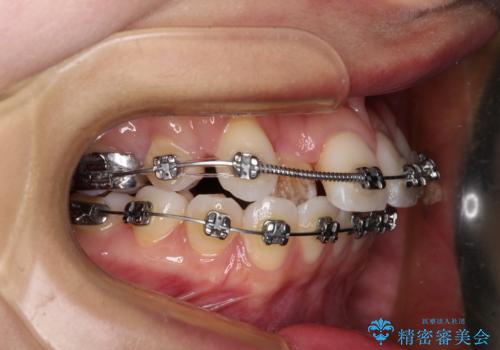

- 矯正装置

- メタルブラケット

奥歯の咬み合わせを維持しながら正中位置を改善するために、補助装置を使用しました。

予定より期間がかかりましたが、上下の正中位置を綺麗に一致させることができました。